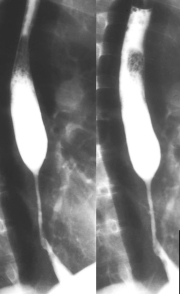

Image

radiologique de l'oesopagite de reflux sur TOGD de

double de contrast : Ouverture de angle de His

,petites ulceres et epaissisement de plie muqueuse

oesophagien etre en voyant. |

Stenose circonferentiele symetrique a distal de

oesophage . Technique radiologique TOGD +

technique de double de contrast baryte de oesophage

. . |

radiologique en double de contrast d'une stenose a

distal : oesophagite de reflux au grade 4

endobrachyoesophage(EBO) |